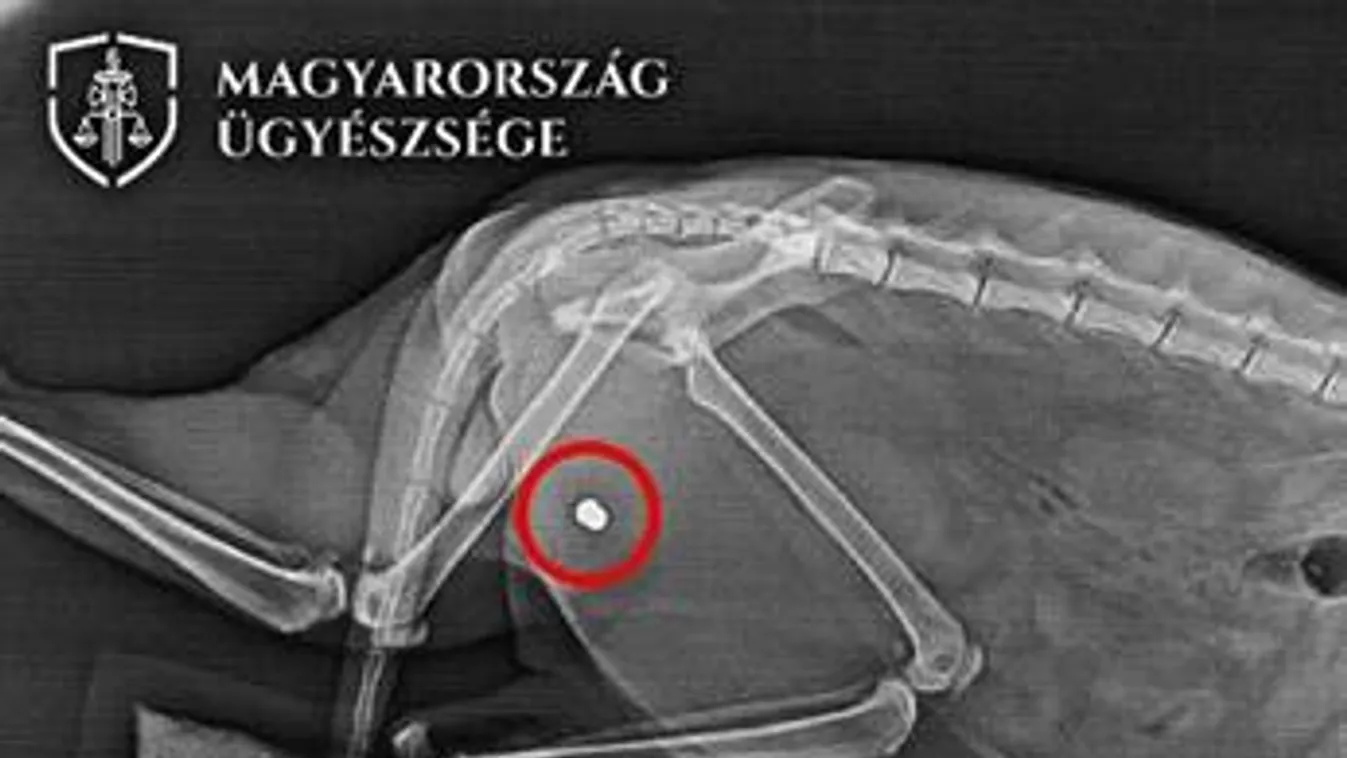

Légpuskával lőtte meg a szomszéd macskáját